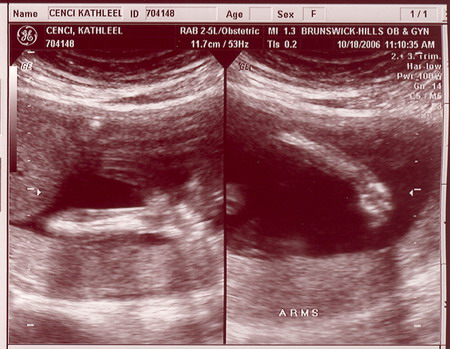

| On October 18, 2006 we had the second sonogram. The baby is growing well. It was moving quite a bit while we were watching. It is amazing to actually see feet, arms, ribs, the spine, we even saw it sucking it's thumb. Check out the photos below. Each one is clickable which will bring you to labeled versions to help you identify what you're looking at. Enjoy! |

Click on any/all of the photos above to see more. The links will give you full resolution photos and labeled versions. The labeling is my best guess as to what your looking at. We saw much more on the monitor, the motion version was awesome.